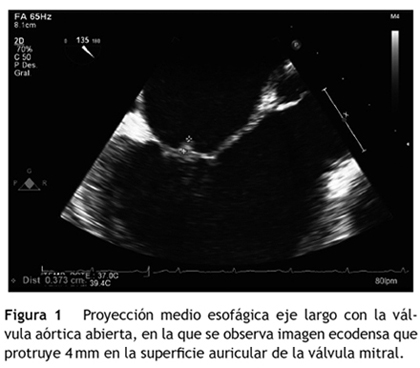

Desde su ingreso presentó picos febriles, por lo que se solicitaron hemocultivos y ecocardiografía transesofágica; esta última reportó engrosamiento del cuerpo de la valva anterior de la válvula mitral (grosor hasta de 6,0 mm), imagen ecodensa que protruía 4,0 mm en la superficie auricular de la válvula compatible con vegetación, insuficiencia mitral trivial con origen en la superficie de coaptación y derrame pericárdico trivial (fig. 1).

Una semana después se realizó ecocardiografía transesofágica de control que reportó disminución del grosor de la valva anterior de la mitral (entre 4,0 y 6,0 mm) y resolución de la vegetación evidenciada (figs. 2 y 3).